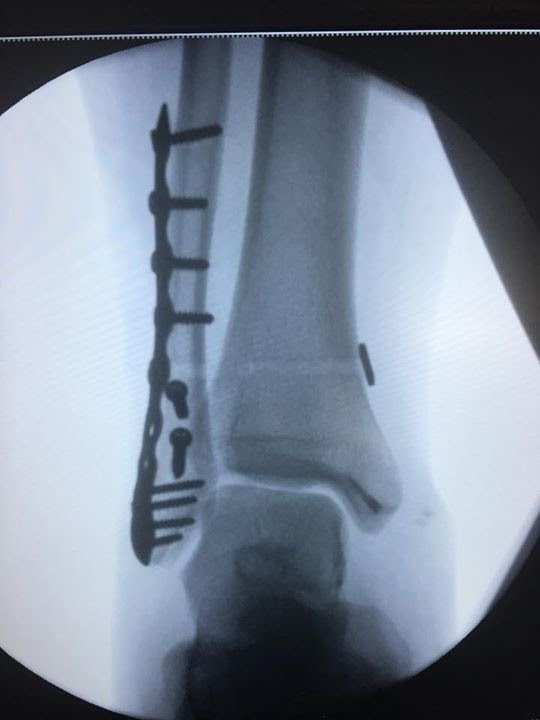

Fractura de tobillo